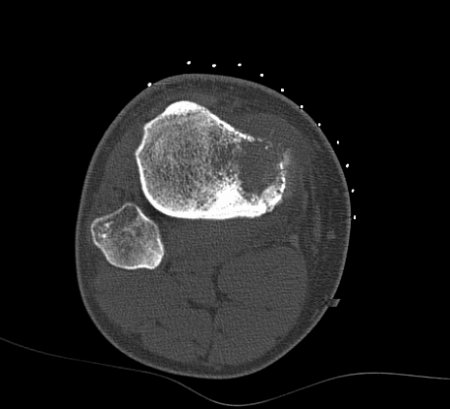

Matrix production by the tumour and the extent of cortical destruction are best appreciated on CT scans. A CT-guided biopsy can be performed simultaneously. If the tissue obtained is diagnostic, an open biopsy is not necessary and a treatment plan can be designed. If the tissue obtained is not diagnostic, an open biopsy is required.[Figure caption and citation for the preceding image starts]: Computed tomographic scan, axial view; osteosarcoma of proximal tibia; matrix production and bone destruction are best appreciated on conventional tomographsPersonal collections of Dr Michael J. Klein and Dr Luminita Rezeanu [Citation ends].

Result

findings vary with exact type of tumour; shows dense bony mass; may show central calcification, cortical destruction